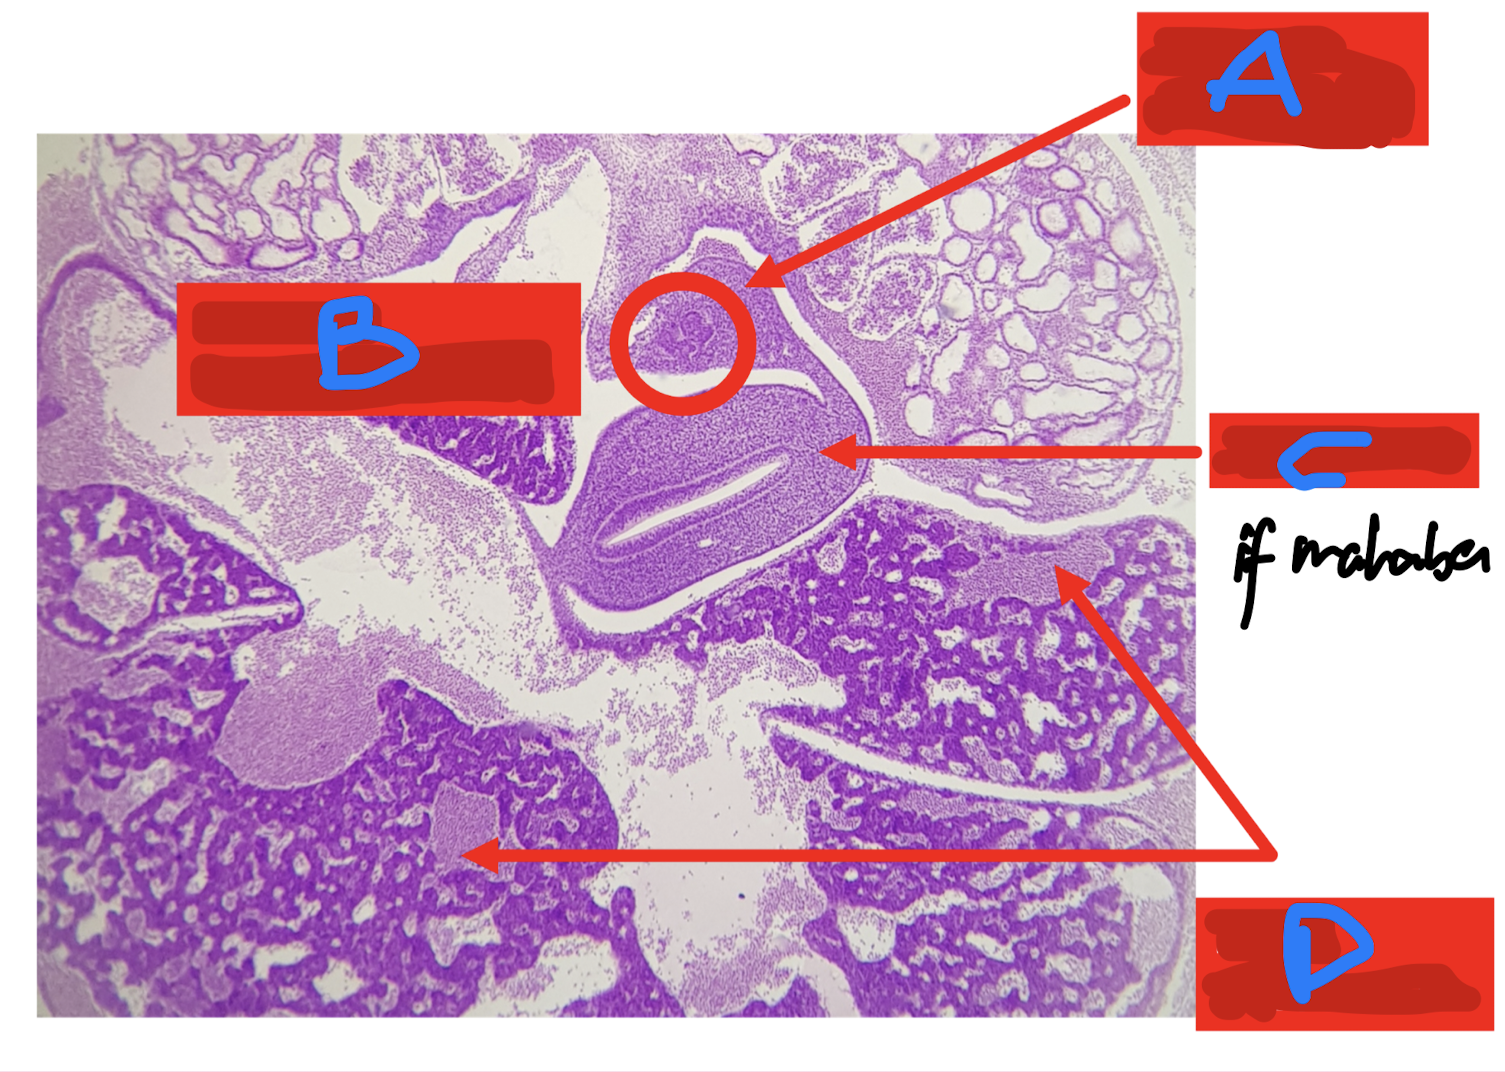

Identify the structure

A: duodenum

B: cystic duct

C: gallbladder

D: liver